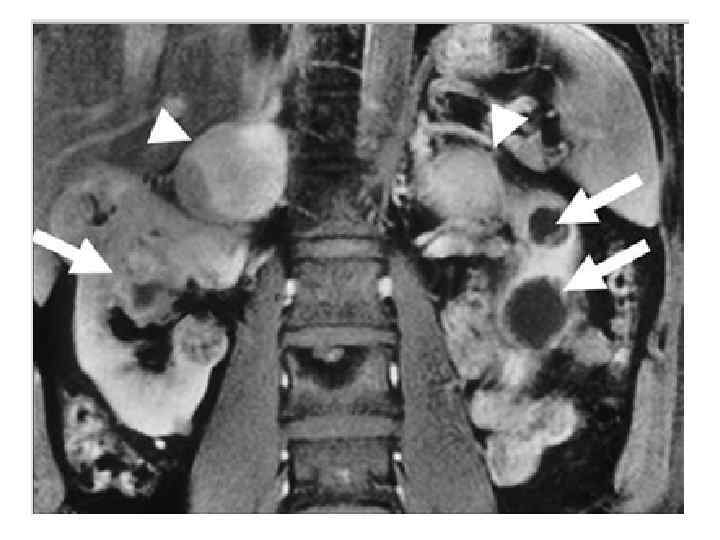

Топическая диагностика ФХЦ/ПГ • Только при наличии лабораторных данных о диагностически значимом повышении метанефринов! • МРТ: при параганглиомах головы и шеи, а также при строгом индивидуальном ограничении лучевой нагрузки. • КТ: феохромоцитомы органов грудной клетки, брюшной полости и малого таза

Феохромоцитома (ФХЦ) • Феохромоцитома – это опухоль мозгового слоя надпочечника, состоящая из хромаффинных клеток, продуцирующая катехоламины (адреналин, норадреналин и дофамин). • Параганглиома – это опухоль, состоящая из вненадпочечниковой хромаффинной ткани симпатических паравертебральных ганглиев грудной клетки, брюшной полости и таза.

80– 85% опухолей хромаффинной ткани – феохромоцитома 15– 20% – параганглиома